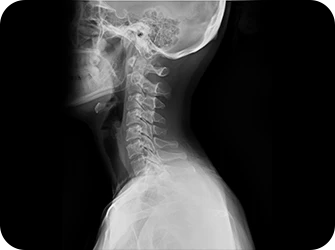

이제는 하세요!

엑스레이 검사

CT 검사

MRI 검사